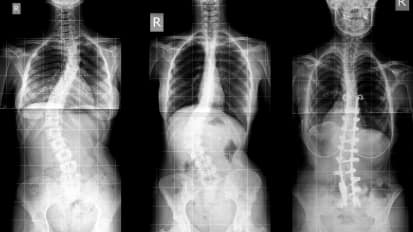

MUSC Children’s Health pediatric orthopaedic surgeon Robert F. Murphy, M.D., discusses treatment options for patients with scoliosis, from bracing to surgery, and when each is indicated. Murphy details the goals of corrective surgery for scoliosis.